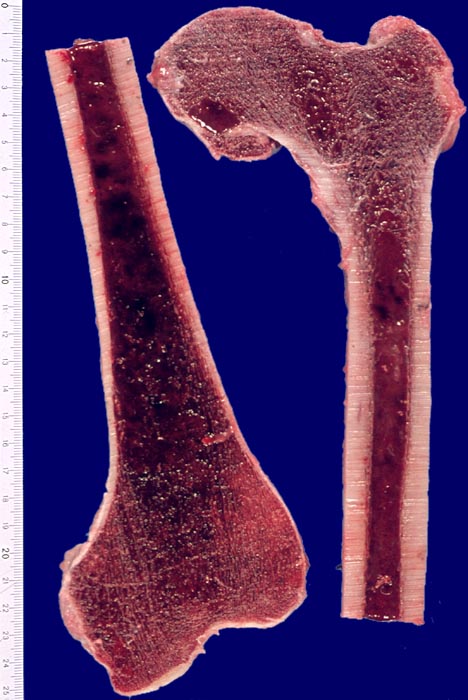

PathoPic – image database / PathoPic ID 3847 - Akute myeloische Leukämie: Hyperplastisches Knochenmark

Akute myeloische Leukämie: Hyperplastisches Knochenmark

Knochen, Femur

Das gesamte Mark des Femurknochens (im Normalfall nur das proximale Drittel bis etwa die Hälfte) ist blutbildend und aus diesem Grund dunkelrot gefärbt.

Im Normalfall enthält das proximale Drittel bis etwa die Hälfte des Femurknochens beim Erwachsenen blutbildendes Mark, der Rest besteht aus gelbem Fettmark.